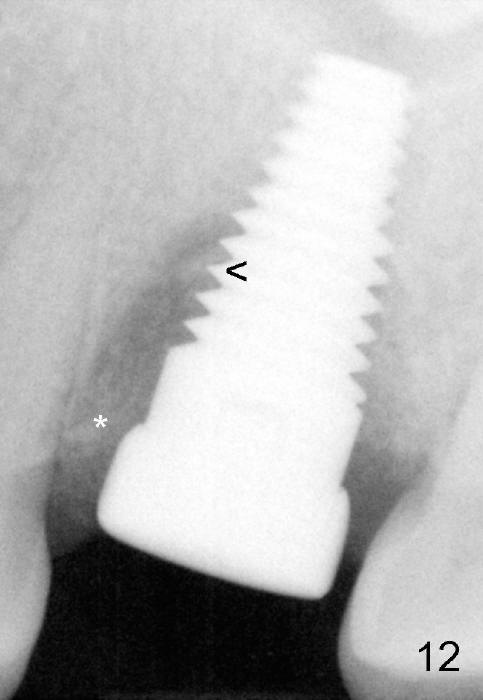

Bone appears to regenerate in the apical aspect of the mesial gap 5.5 months postop (Fig.12 <). The implant remains stable and is ready for restoration. The peri-implant radiolucency continues to reduce 1 year post cementation (Fig.13).